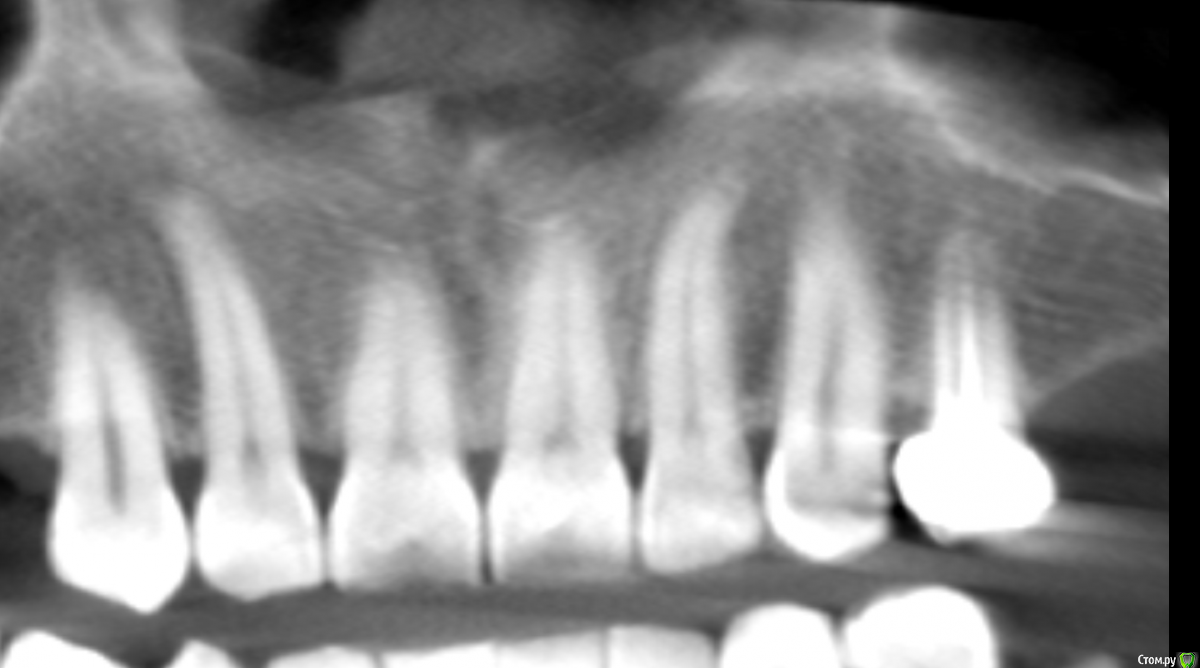

Дмитрий Л. Опубликовано 9 июня, 2018 Поделиться Опубликовано 9 июня, 2018 Я сам решил просто рассечь и удалить эту гадость но честно говоря смушают размеры и плюс случай такой первый раз лишний опыт не помешал бы.Спасибо.Научить чистить зубы.Рассекать смысла большого нет, может сильно кровить.Высечь до кости, бором или фрезой обработать +- милиметр кортикалки и под йодоформным тампоном провести.Гистология.Эндодонтия 21. 2 Ссылка на комментарий

Дмитрий Л. Опубликовано 11 июня, 2018 Поделиться Опубликовано 11 июня, 2018 Зачем? Зачем?! Будет дефект слизистой и оголённая кость. Как бы вы предложили вести такую рану? Как вы считаете, какая этиология эпулида в данном случае? Есть ли причинный зуб? Какой вообще диагноз и лечение вы бы предположили / предложили? Ссылка на комментарий

Irouil Опубликовано 11 июня, 2018 Поделиться Опубликовано 11 июня, 2018 На дворе вроде 21 век, зачем йодоформ? Большой дефект - лоскут, трансплантат, небольшой дефект - мобилизация, самозаживетизация. Я бы перед эндо как минимум провел ЭОД. Ссылка на комментарий

Дмитрий Л. Опубликовано 12 июня, 2018 Поделиться Опубликовано 12 июня, 2018 На дворе вроде 21 век, зачем йодоформ? Большой дефект - лоскут, трансплантат, небольшой дефект - мобилизация, самозаживетизация. Я бы перед эндо как минимум провел ЭОД.Да, здесь есть варианты, и я надеюсь автор темы не будет слепо следовать рекомендациям (в т.ч. моим). Ссылка на комментарий